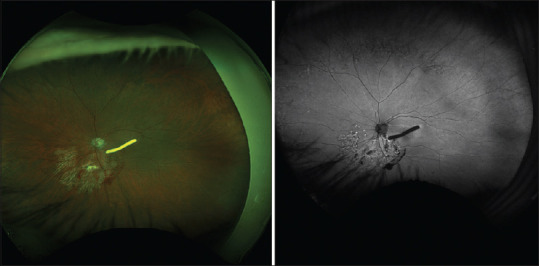

Foveal adhesion of a dexamethasone implant: Evaluation and follow-up via multimodal imaging.